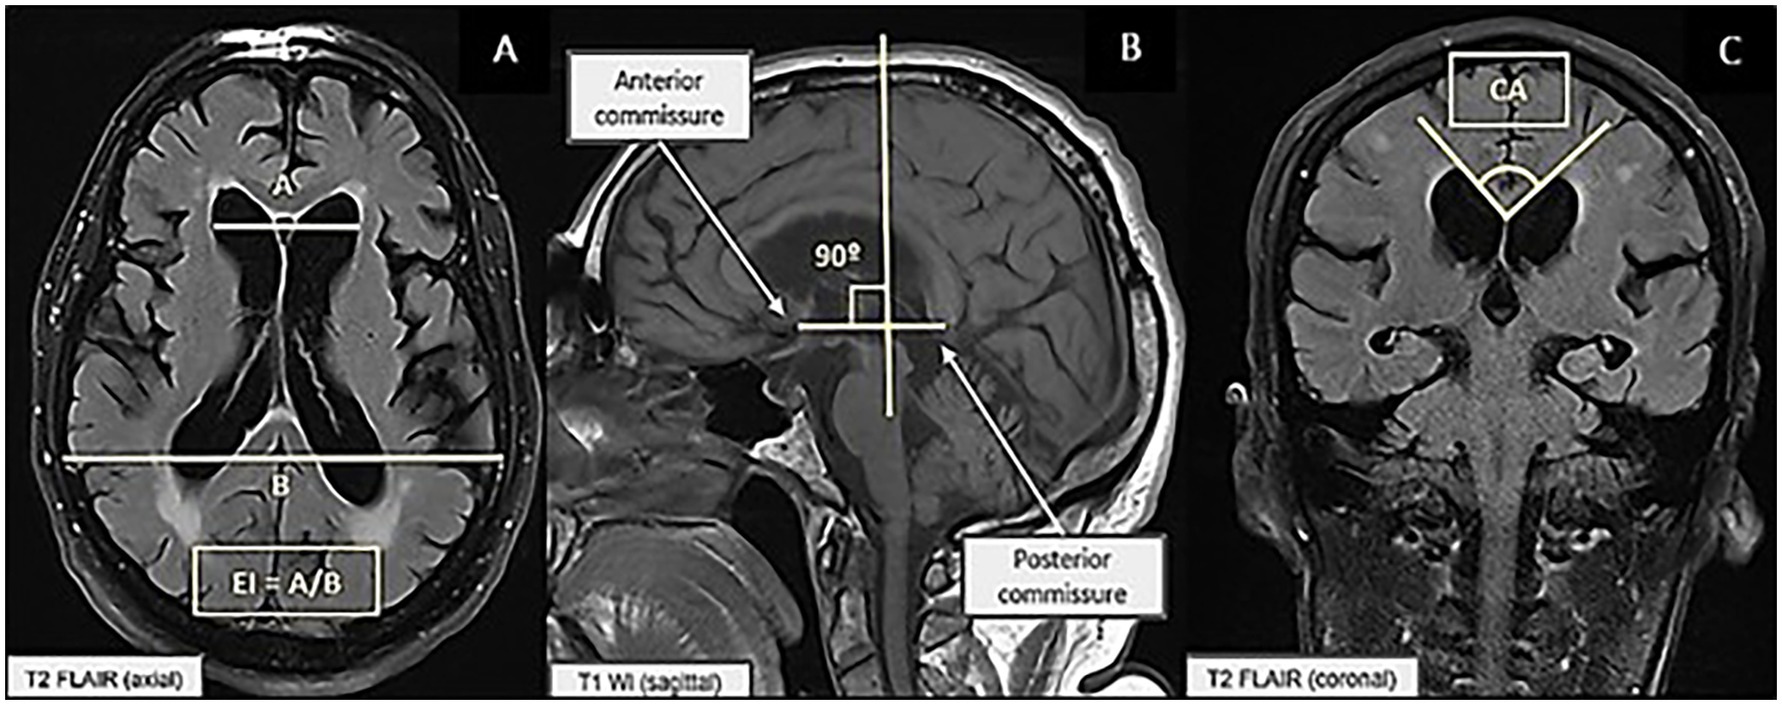

The EI was calculated in the axial plane by measuring the maximum width of the frontal horns divided by the maximum width of the inner skull in the horizontal plane, measured at the level of the III ventricle, with values > 0.3 indicating ventriculomegaly (Nakajima et al., 2021) (Figure 1A). The CA was calculated in the coronal plane, perpendicular to the anterior commissure–posterior commissure line, at the level of the posterior commissure and between the medial walls of the lateral ventricles, with a steep angle defined as < 90° (Nakajima et al., 2021) (Figures 1B,C).

Figure 1. (A) Measurement of the Evans index. (B) Measurement of the callosal angle on sagittal T2 FLAIR (Fluid-Attenuated Inversion Recovery) brain MRI. (C) Measurement of the callosal angle on coronal T1-weighted brain MRI.